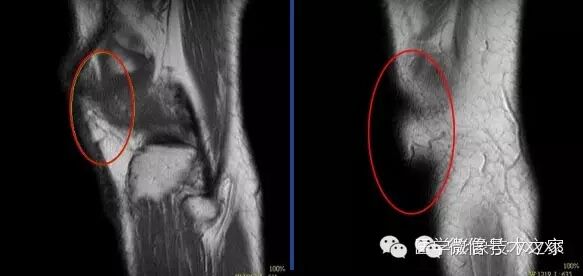

伪影较细小,出现在图像的局部,可能比较模糊,甚至需要在特殊窗宽窗位下才能发现。

Zip512可以使伪影更佳明显。